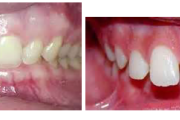

Sügav hambumus

Normaalse jäävhammaskonna pilt küljelt ja eest vaadatuna.